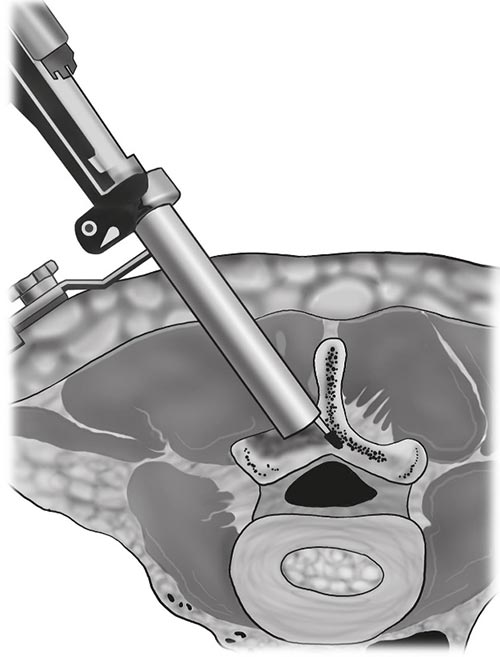

O tratamento da estenose lombar por via endoscópica é muito recente, seus resultados a longo prazo ainda são desconhecidos, estudos recentes são promissores, porém seu alto custo e longa curva de aprendizado ainda são pontos negativos. A técnica tem se tornado mais frequente devido a experiência adquirida no tratamento das hérnias discais, materiais específicos como brocas especiais e eletrocautérios por radiofrequência, óticas e iluminações próprias tem sido desenvolvida. As abordagens possíveis são a descompressão endoscópica interlaminar, transforaminal, e foraminotomia endoscópica, a escolha da técnica depende do tipo e local da estenose.

Komp et al publicou um estudo prospectivo randomizado de 135 pacientes comparando a descompressão bilateral por técnica totalmente endoscópica por abordagem unilateral, com a descompressão por laminotomia bilateral, acompanhados por 2 anos. Em ambos os grupos houve uma melhora clínica sem diferença estatisticamente significante, porém na cirurgia endoscópica o número de complicações e necessidade de reoperação foram menores, o tempo de internação e duração da cirurgia também foram menores nos pacientes operados pela técnica endoscópica.

Descompressão lombar interlaminar com auxílio endoscópico.